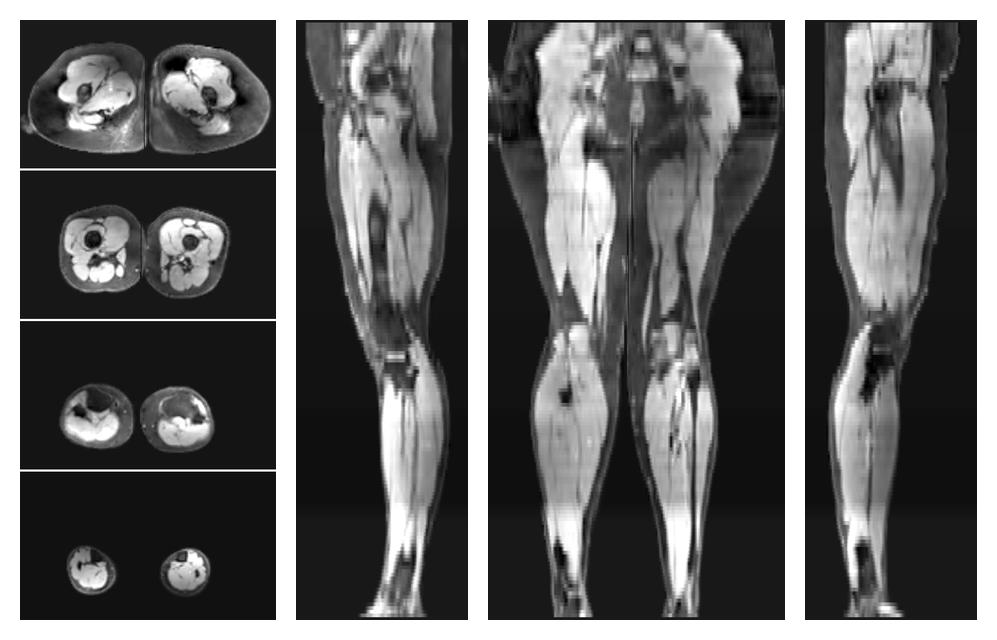

• Water only signal

The water part of the acquired multi-echo spin echo data.